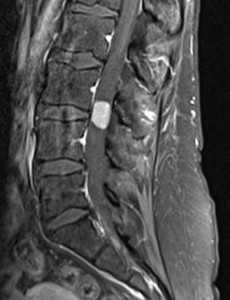

(Слева) Сагиттальный срез, Т1-ВИ: объемное образование вида «цветной капусты», характеризующееся гетерогенной интенсивностью сигнала, исходящее из левого дугоотростчатого сустава L5-S1. Гиперинтенсивность Т1 -сигнала отражает элементы костного мозга.

(Справа) Фронтальный КТ-срез: остеохондрома, исходящая из левых задних элементов грудного позвонка. Кортикальная пластинка и костномозговое пространство образования являются непосредственным продолжением таковых у подлежащей кости. Смежные ребра оттеснены.